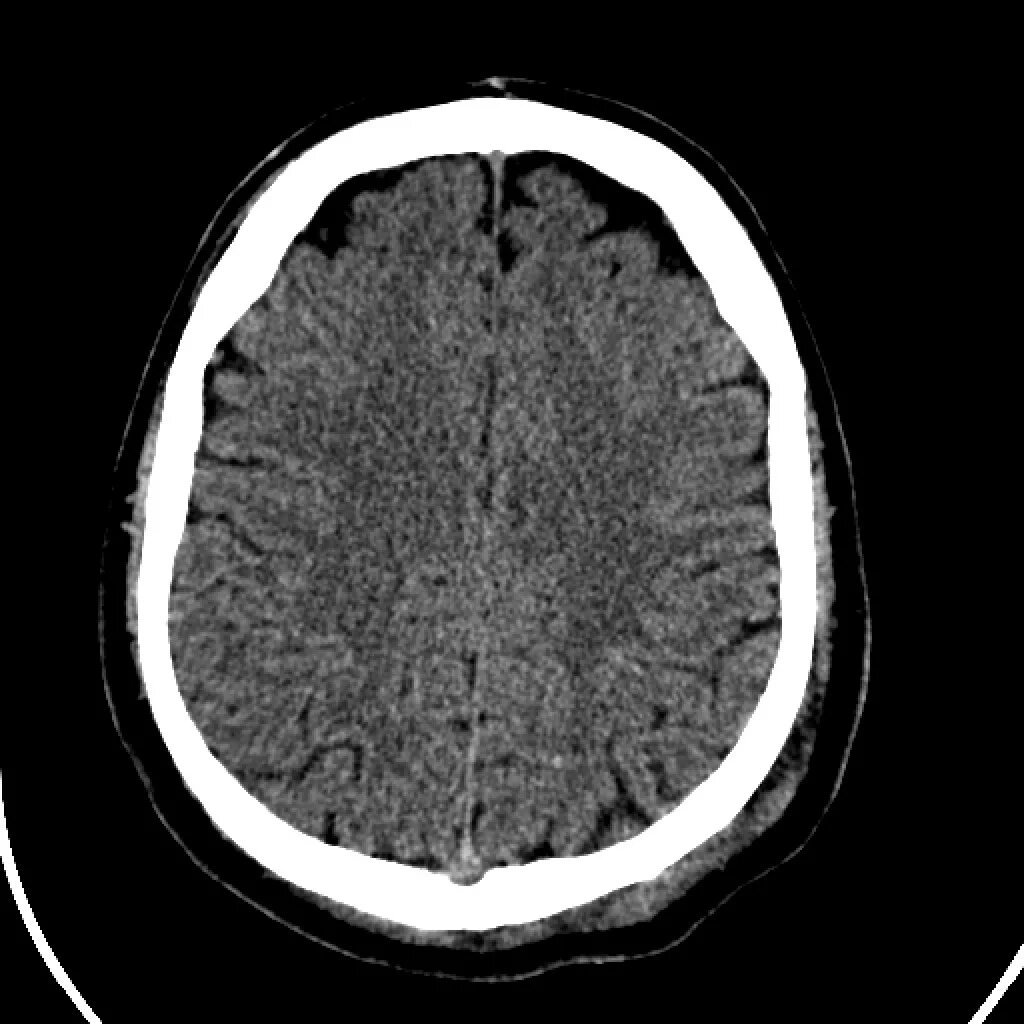

Brain 98